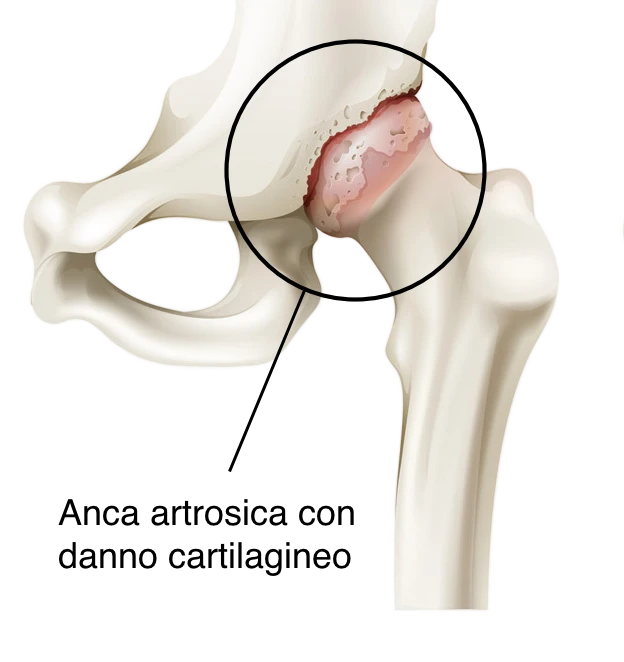

- Artrosi primaria avanzata con dolore meccanico quotidiano, rigidità, limitazione marcata del cammino.

- Coxartrosi secondaria (esiti di displasia, conflitto femoro–acetabolare, post-traumatica).

- Dolore refrattario a ≥ 3–6 mesi di trattamento conservativo (farmaci, fisioterapia, perdita di peso, ausili)

- Limitazione funzionale importante (difficoltà ad allacciarsi le scarpe, salire/scendere le scale, camminare > 200–300 m)

- Radiografie con riduzione dello spazio articolare, osteofiti, geodi, deformità della testa femorale